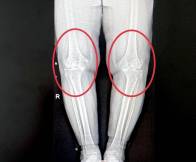

2025-12-10协和医生辟谣:骨关节炎真的是冻出来的吗?